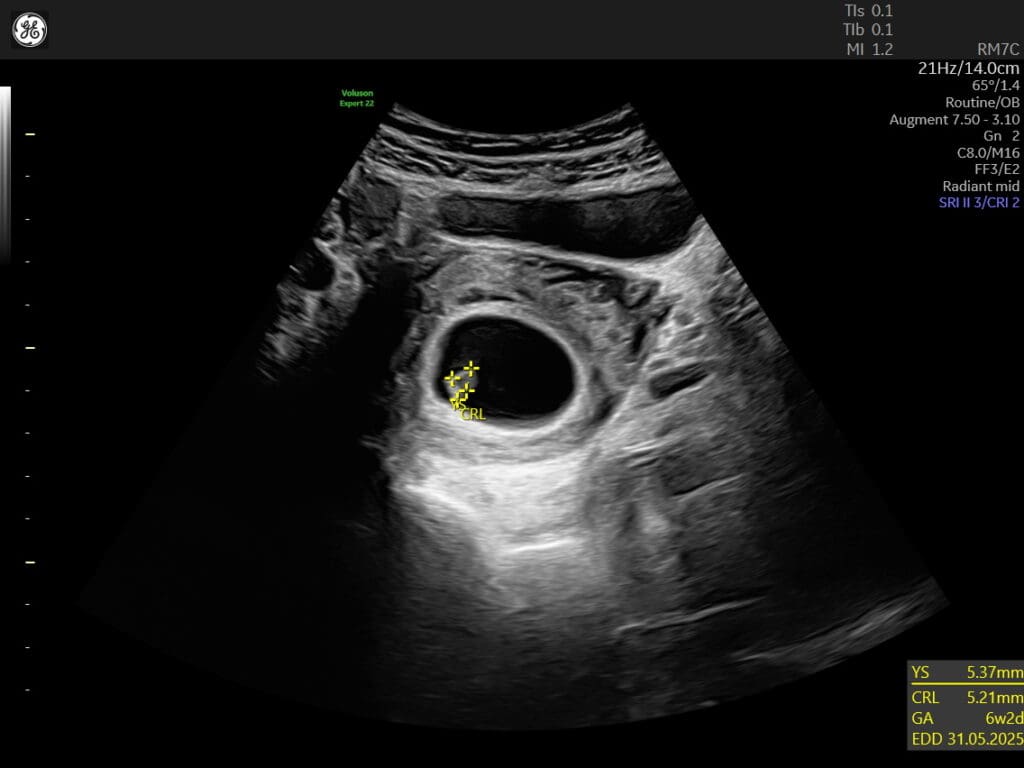

The viability scan is usually conducted between 6 to 10 weeks of gestation. It aims to confirm the presence of a gestational sac, which is a fluid-filled structure where the baby develops, and to detect the baby’s heartbeat. This scan helps determine if the pregnancy is progressing as expected and if the baby is growing properly.

During the scan, a healthcare professional will use an ultrasound machine to carefully examine the uterus and the gestational sac. They will look for the presence of a yolk sac, which provides nourishment to the developing embryo, as well as the fetal pole, which contains the early stages of the baby’s body.

The detection of a heartbeat is a significant milestone in the viability scan. It indicates that the baby’s heart has started beating, which is a reassuring sign of a healthy pregnancy. Additionally, the scan may also provide an estimated gestational age, which helps in determining the due date and tracking the progress of the pregnancy.